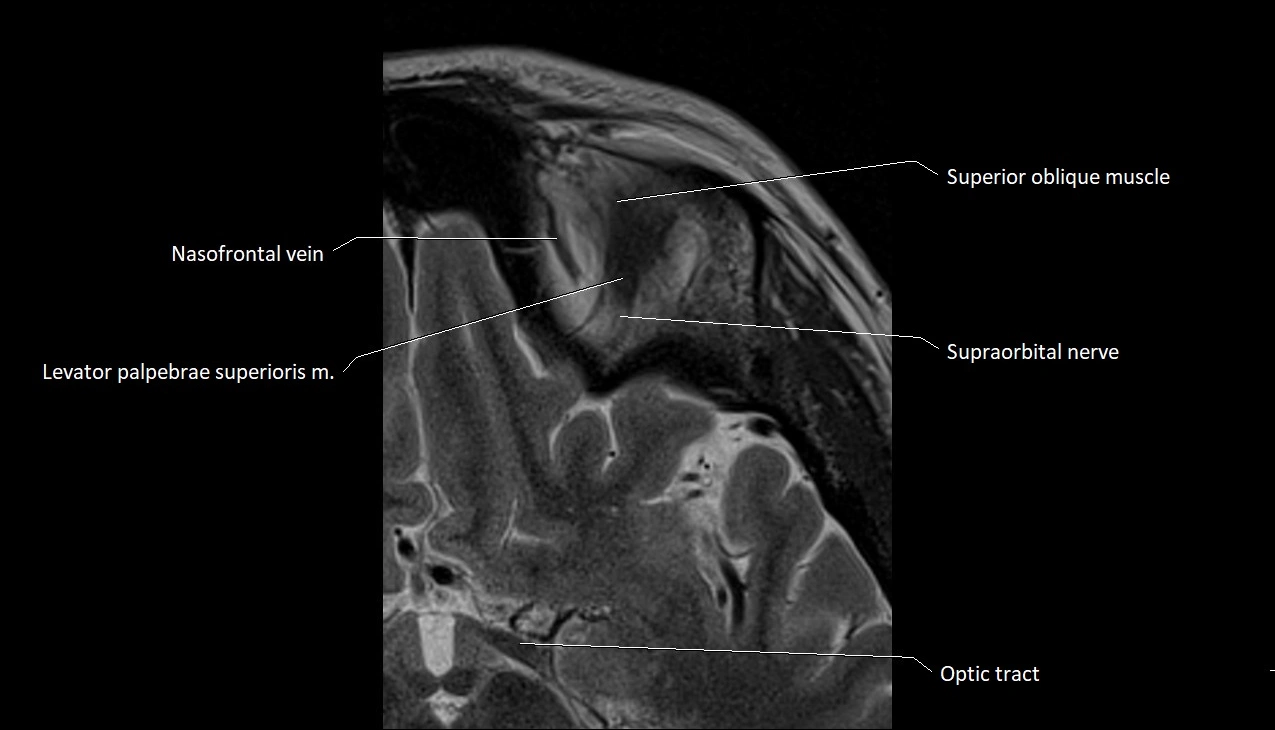

- Levator palpebrae superioris muscle

- Nasofrontal vein

- Superior oblique muscle

- Supraorbital nerve